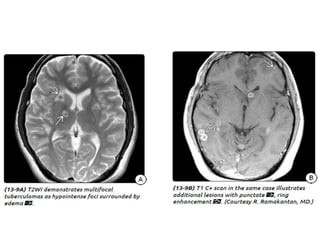

Tuberculous meningitis

• Tuberculous meningitis is the most common presentation

of intracranial tuberculosis, and usually refers to infection of

the leptomeninges.

• Tuberculous meningitis, although seen in all age groups, has a

peak incidence in childhood (particularly 0-4 years of age) in

high prevalence areas.

Tuberculous meningitis • Tuberculousmeningitis is the most common presentation of intracranial tuberculosis, and usually refers to infection of the leptomeninges. • Tuberculous meningitis, although seen in all age groups, has a peak incidence in childhood (particularly 0-4 years of age) in high prevalence areas.